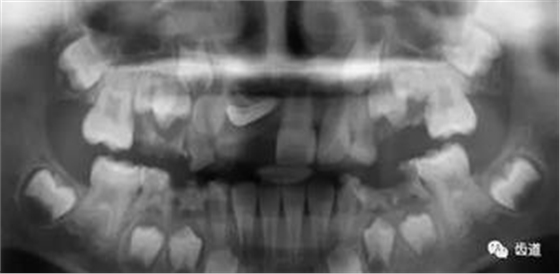

三)種植修復(fù)

CBCT在牙種植修復(fù)中的應(yīng)用。種植前利用CBCT對(duì)患者的牙床進(jìn)行檢查,可精準(zhǔn)判斷牙槽骨的寬度、厚度及高度、骨的密度、重要的顏面神經(jīng)、血管和鼻竇位置等。臨床醫(yī)生不僅可以在計(jì)算機(jī)直觀的看到牙槽骨的立體影像,還可以切換不同的視角來(lái)觀察硬組織之間的位置關(guān)系,在手術(shù)方案中避開危險(xiǎn)區(qū)域,保證手術(shù)的安全性。臨床醫(yī)生還可以利用CT數(shù)據(jù)進(jìn)行數(shù)字模型重建,配合軟件預(yù)先做好手術(shù)模板,使種植手術(shù)更安全快捷,避免在種植手術(shù)過(guò)程中不慎破壞神經(jīng)、鼻竇等解剖結(jié)構(gòu),導(dǎo)致顏面神經(jīng)麻痹、鼻竇炎等并發(fā)癥的發(fā)生。

1、下頜骨種植牙前測(cè)量準(zhǔn)備影像

2、上頜骨種植牙前準(zhǔn)備影像

3、下頜骨種植牙術(shù)后